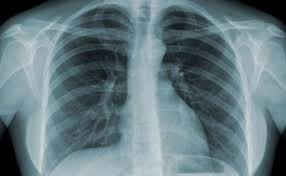

Khi chụp X-quang thấy có vết mờ trên phổi bị nghi ngờ là ung thư có thể làm thêm các xét nghiệm khác nhằm xác định một cách chính xác.

TS.BS Đặng Văn Khiêm, Trưởng khoa U bướu, Bệnh viện Lao và các bệnh phổi T.Ư: Khi chụp X-quang thấy có vết mờ trên phổi bị nghi ngờ là ung thư có thể làm thêm các xét nghiệm khác nhằm xác định một cách chính xác.

Như chụp cắt lớp lại phổi để xác định chính xác hơn vết mờ trên phổi, đồng thời cần siêu âm, soi phế quản, chọc sinh thiết khối u để làm các xét nghiệm mô bệnh học nhằm xác định vết mờ trên phổi có phải là ung thư hay không.

Với cách phát hiện sớm này sẽ giúp người bệnh nếu bị ung thư khả năng khỏi và kéo dài tuổi thọ sẽ cao hơn.